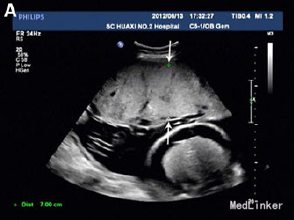

31岁女性,G2P1,孕31周,因高血压、少尿、胎儿和胎盘水肿就诊

实验室检查提示Hb 80g/L,极低的血清铁蛋白 超声提示严重腹水、心肌肥大、心包积水,羊水过多,但无皮肤水肿 轻微胸腔积水 病毒感染检查提示均为阴性 初步诊断为子痫前期、胎儿水肿和缺铁性贫血 孕妇外周血压114-138/67-92 口服降压药,注射地塞米松 入院4天出现咳嗽,不伴干湿罗音,四肢水肿加重,血压升到142-165/95-100,Hb 72g/L

孕31+4周时诱发生产 第二产程时,出现严重的呼吸困难和血压升高(177/120) 给予呋塞米静注 可见婴儿头部,故继续阴道分娩,助产 产下一男婴2200g,Apgar评分分别为2,2 胎盘巨大,重1250g 新生儿22min后死亡 尸检提示心肺衰竭死亡 最后诊断为镜像综合征